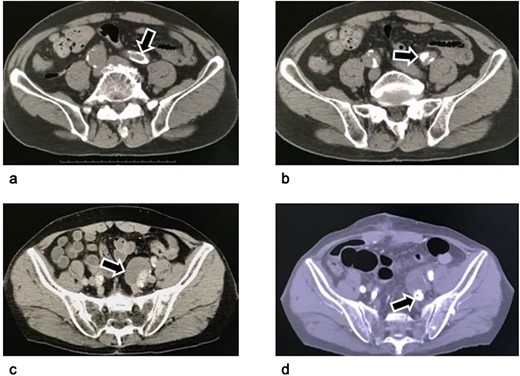

We decided to perform hybrid therapy. In the first stage, we performed endovascular embolization of the distal branches of the left internal iliac artery aneurysm. We inserted a 5 Fr guiding sheath (Destination® Guiding Sheath, Terumo, Tokyo, Japan) into the left common femoral artery under local analgesia. The two branches distal of the internal iliac artery, that is the posterior and anterior divisions of the distal left internal iliac artery, were ebmolized. First, the posterior division was embolized with 3*60 mm, 4*80 mm, 6*100 mm and 8*20 mm microcoils (Interlock™ Fibered IDC Occlusion System, Boston Scientific, Marlborough, MA, USA). Ten-mm and 12-mm vascular plugs (Amplatzer™ Vascular Plug II, St. Jude Medical, Inc., Saint Paul, MN, USA) was deployed into the anterior division of the internal iliac artery and the internal iliac artery stem distal to the aneurysm (Figure 2). The patient was discharged without any complications and did not complain of buttock claudication.

Arteriogram of the left internal iliac artery during the embolization procedure as the first stage of hybrid intervention. (a) Arteriogram before embolization: The left internal iliac artery stem distal to the aneurysm (black triangle) and the anterior (white arrows) and posterior division of the internal iliac artery (black arrows) are shown. (b) Arteriogram after coiling of the posterior division of the left internal iliac artery: Metal coils are visible from the posterior division of the left internal iliac artery to the superior gluteal artery. The microcoil was used because it provides good control in these narrow and tortuous arteries. (c) Arteriogram after vascular plug deployment: The left internal iliac artery stem and its anterior division were embolized using an Amplatzer vascular plug because they were wide and straight enough to insert the 5 Fr guiding catheter. Triangles: the vascular plug. The black arrows indicate the tip of the plug. The blood flow in the artery persisted after the plug had been deployed. The completion of embolization with metal devices needs time.